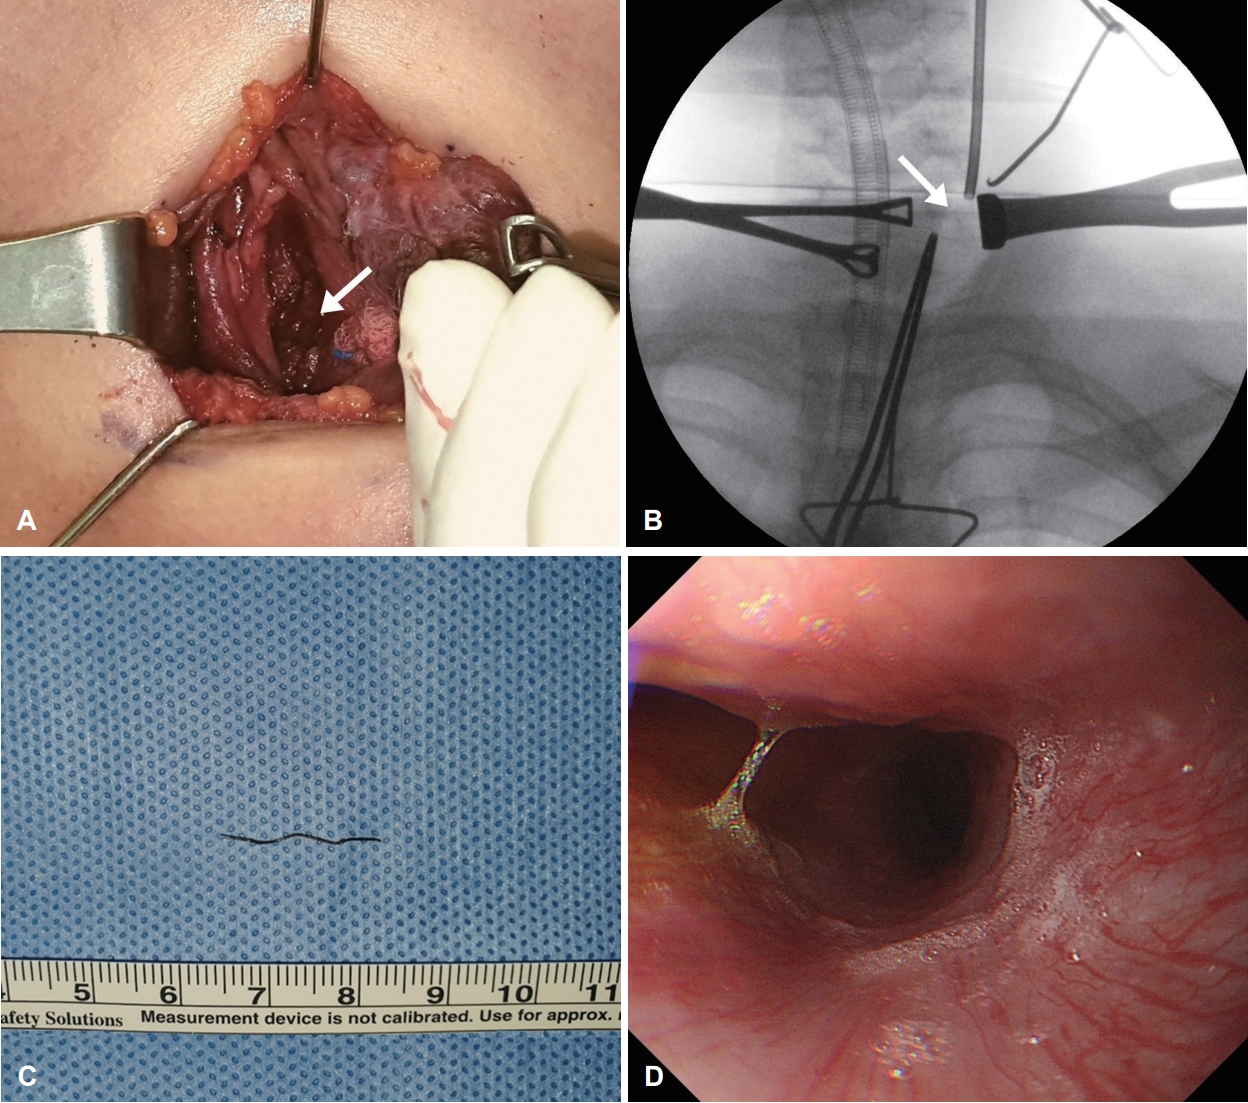

전신마취하에 흉골 상방 위에 수평 절개를 시행하였으며, 좌측 갑상선을 내측으로 당기며, 경동맥을 외측으로 당겨 경장근을 노출시켰다(Fig. 2A). 육안상, 경부 공간으로 노출된 이물은 없었으며, 촉진 시에도 이물이 확인되지 않았다. 이물의 정확한 위치를 파악하기 위해 수술 중 digital fluoroscopy, X-ray 투시 장치(C-arm) 방사선 투영하 위치를 확인하였다. C-arm 방사선 투영은 본과에서 조작하였다. 이물은 근육의 깊은 안쪽에 위치하는 양상이었으며, C-arm 투영법으로 정확한 위치를 확인하여 근육에 절개를 가한 후 근육 섬유를 박리하여 겸자로 제거하였다(Fig. 2B). 제거된 이물은 2 cm 크기의 1 mm 반경의 얇은 금속 물질(철사 수세미)로(Fig. 2C), 제거 후 근육과 식도와의 연결부위 및 누공은 확인되지 않았다. 또한 식도의 천공 의심 소견은 보이지 않아 추가적인 식도 위의 봉합 및 지혈제는 사용하지 않고, 경부 절개 부위에 대해서만 피부 봉합을 시행하여 수술을 마쳤다. 수술 시간은 총 1시간 30분 소요되었으며, 수술 이후에도 수술부위의 염증 및 합병증은 발생하지 않았다.

술후 4일간 금식 시행하였으며, 수술 후 4일이 경과한 뒤 소아과에 의뢰하여 소화기 위 식도내시경을 시행하였다. 검사상에서 식도 내에서 천공 등의 이상 소견은 확인되지 않았다(Fig. 2D). 입원 중 항생제 7일간 사용하였으며, 무증상으로 퇴원하였다.